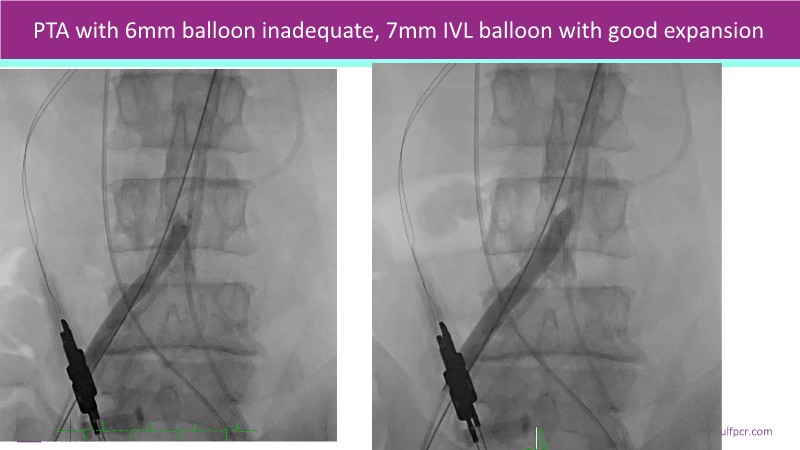

Discover a selection of cases showcasing the key features of the Navitor Valve System and its clinical applications. This session explores auxiliary access, the use of Navitor in alternative access and complex PCI, its performance in challenging peripheral anatomies, and innovative outcomes with the Vantage 30D system.